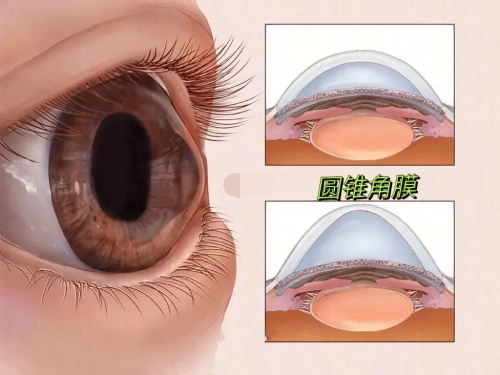

对于高度近视患者而言,眼底检查尤为重要。因为高度近视往往伴随着眼底病变的风险,如视网膜变性、裂孔、黄斑区病变等。如果患者的眼底情况不稳定或存在重度病变,可能需要可靠行干预治疗,待眼底情况稳定后再考虑手术。